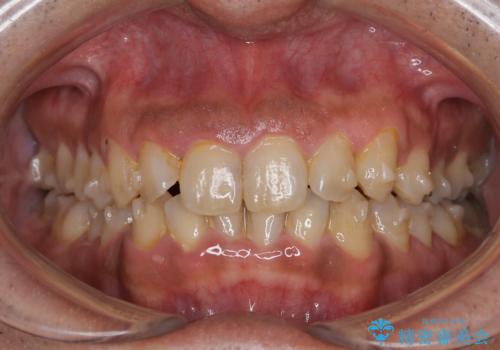

しぶといステインもエアフローワンで1日でキレイに!!

- インビザラインの治療中ですが、歯石やステインが気になるとのことでした。

コーヒーが大好きでよく飲むそうです。

全体的に歯石やステインが付着していたため、エアフロー60分コースを行いました。